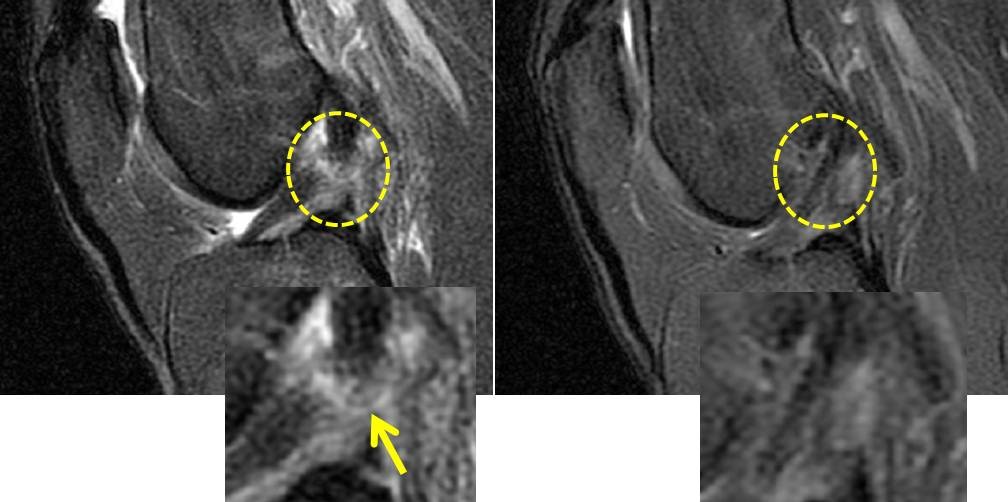

Μερικές εικόνες από μαγνητικές με ρήξη του προσθίου χιαστού συνδέσμου